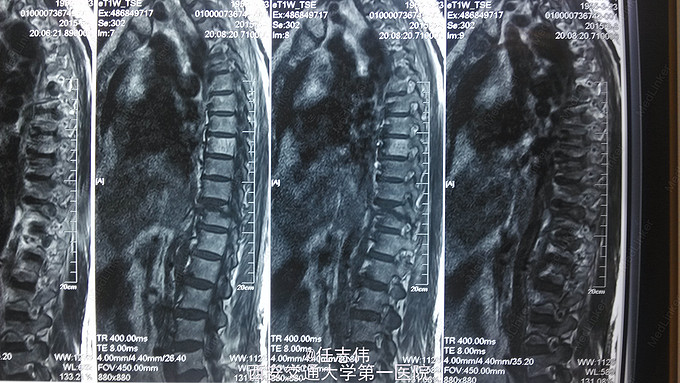

患者女性,60岁,车祸伤致双下肢感觉活动不能8h入院。 8小时前坐农用车时,被横杆撞倒腰部,摔下后感觉胸背部疼痛,双下肢活动不能,伴有短暂昏迷病史。遂来我院就诊。

诊断:1.胸11椎体骨折伴截瘫(Frankel A级)2.闭合性胸部损伤,肺挫伤,多发肋骨骨折,双侧胸腔积液 处理:1.急诊入院告病危,心电血氧监护;2.予以甲强龙冲击治疗;3.次日复查胸部CT,查看肺部损伤情况及胸腔积液,后予以右侧放置闭式引流。患者氧合不稳定,2日后复查胸片胸腔积液减少,予以行后路减压内固定融合术。 手术:术中见局部软组织损伤严重,胸11-12棘上、棘间韧带断裂,胸10、11、12双侧关节突有骨折移位,胸11椎板骨折,胸11左侧不能置入椎弓根螺钉,遂行单纯固定。脊髓局部挫伤明显,并有硬膜破损,予以处理。

术后患者逐渐病情平稳,拔出闭式引流。伤口愈合好。 查体双下肢深感觉有恢复,但肌力仍0级,巴氏征阳性。 1.在没有CT检查时,此骨折容易漏诊,需要注意询问病史,完善检查,尤其是无神经损伤表现者。 2.此患者固定范围应该扩大到腰1吗?还是至胸12就可以了,病椎大家一般都固定吗? 3.对于此例患者大家都急诊手术吗?还是要先处理肺部情况。